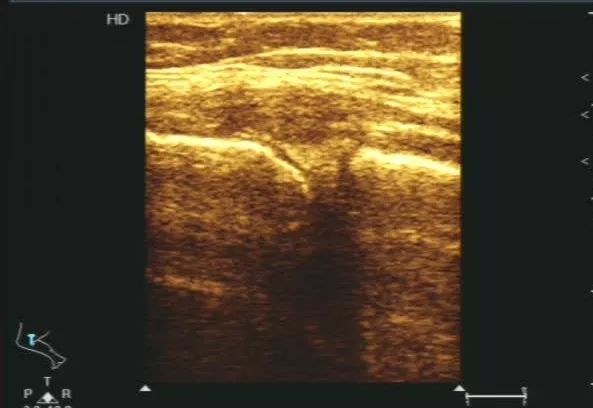

65岁男性患者,碰伤致右胸腹疼痛四天,右胸腹压痛。经肌骨超声检查后提示考虑第七肋骨线性骨折伴软组织肿胀。